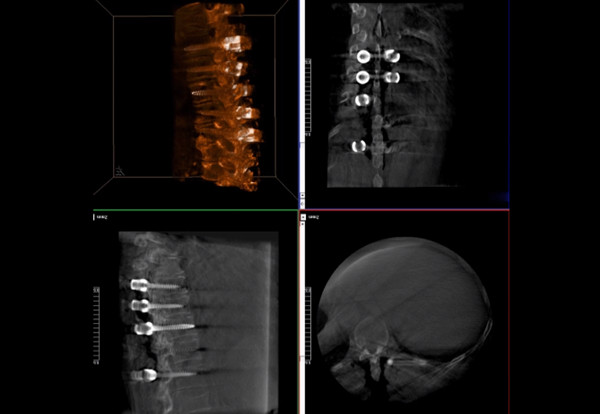

普愛醫(yī)療術(shù)中三維導(dǎo)航C臂快速生成橫斷面、矢狀面、冠狀面斷層圖像和三維立體圖像,方便醫(yī)生確認手術(shù)部位。C形臂的大平板帶來出色的顯示視野,可以更好的顯示手術(shù)部位全局情況,確保手術(shù)規(guī)劃及執(zhí)行的準確性。

三維影像檢驗螺釘植入效果